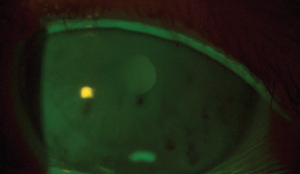

A 68-year-old White woman was referred for persistent keratitis OS and failure on multiple medications. Find out her official diagnosis and treatment plan.